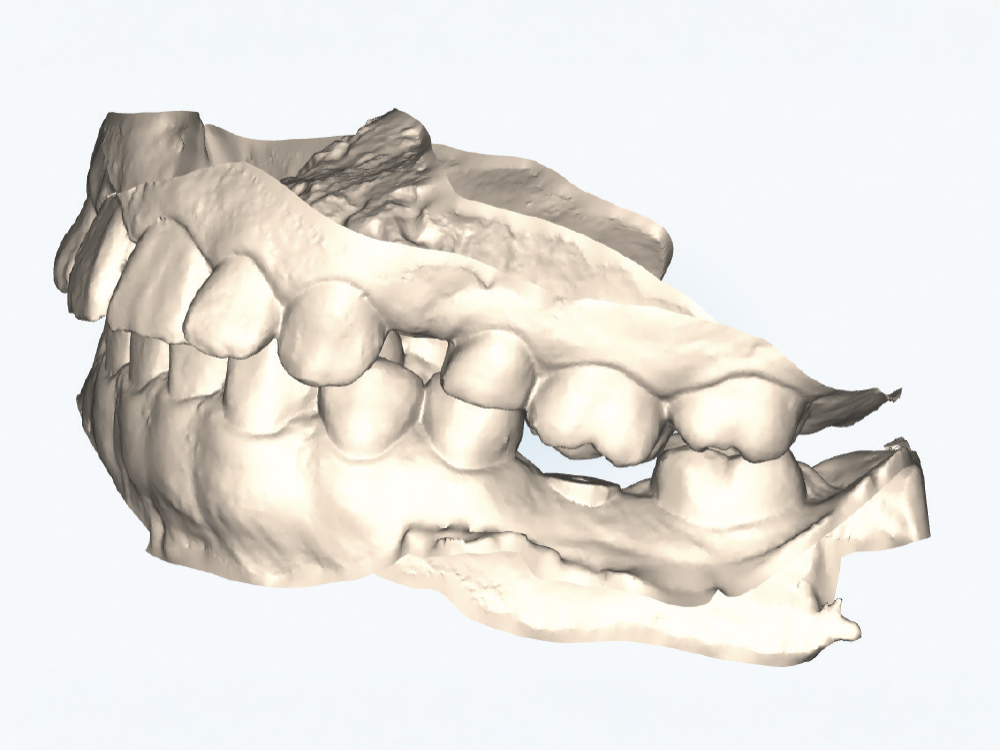

Implant post scan pointing down

Implant post scan close up

Verify the Scans Before Dismissing the Patient. Review all critical areas while the patient is still in the chair, ensuring complete scan body capture, accurate contacts, adequate tissue detail, and proper bite registration. Zoom in on critical areas to verify resolution and completeness. It takes only two minutes to verify a scan, but potentially days before a patient is able to return to your practice. Use the scanner’s analysis tools to identify distortions or artifacts.